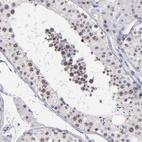

Immunohistochemical staining of human rectum shows moderate positivity in nuclear speckles in glandular cells.